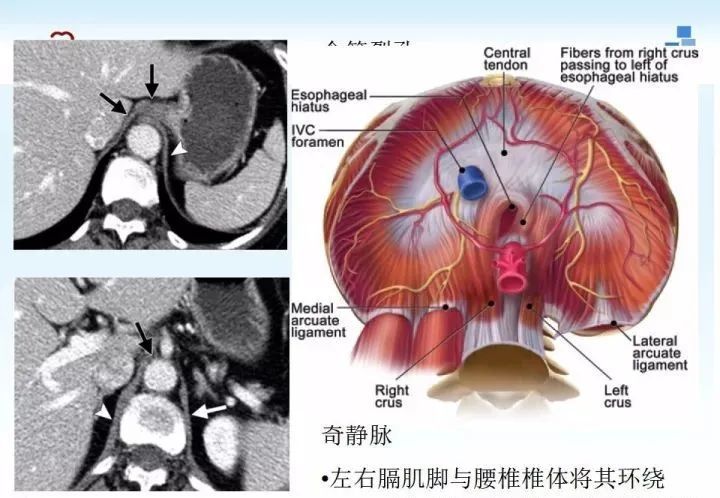

膈肌病变影像

膈肌的解剖及常见病变影像表现